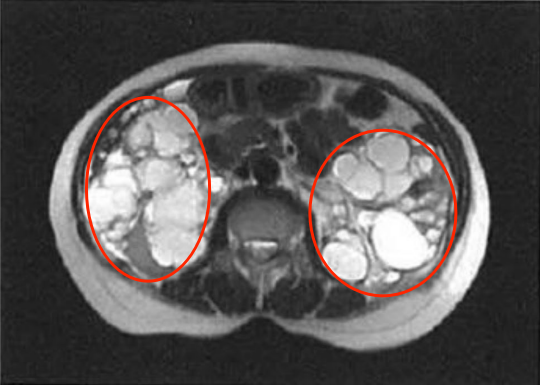

多囊肾和肾囊肿,不是一回事。多囊肾是一种以肾脏遍布多个囊肿、且囊肿不断增大导致肾脏体积不断扩大,最终引起肾功能逐渐下降为特点的遗传性肾病。且该病患者经常在60岁左右时进展迅速。